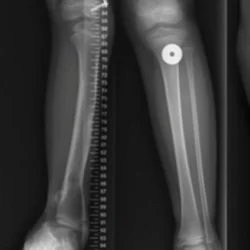

Posteromedial Bow

Tibial Hemimelia

Post Traumatic Deformity